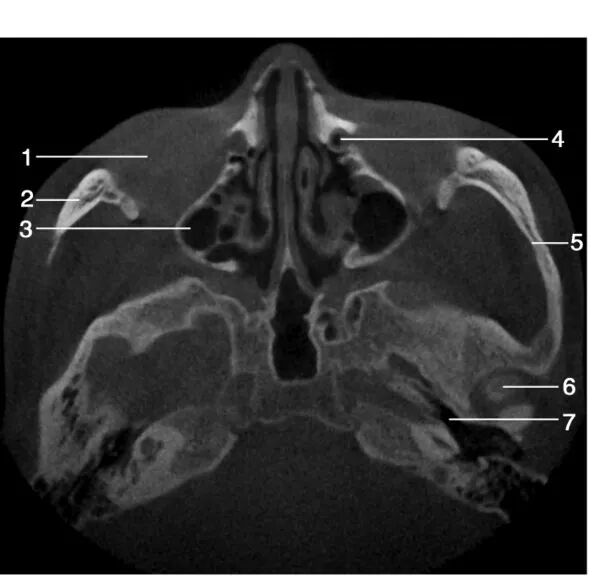

1.右侧上颌窦( right maxillary sinus) ; 2.下鼻甲( inferior turbinate) ; 3.腭中缝( median palatine suture) ; 4.上颌第二前磨牙( maxillary second premolar) ; 5.鼻中隔( nasal septum) ; 6.上颌窦内壁( inner wall of maxillary sinus) ; 7.犁骨( vomer) ;8.上颌牙槽骨( maxillary alveolar bone)